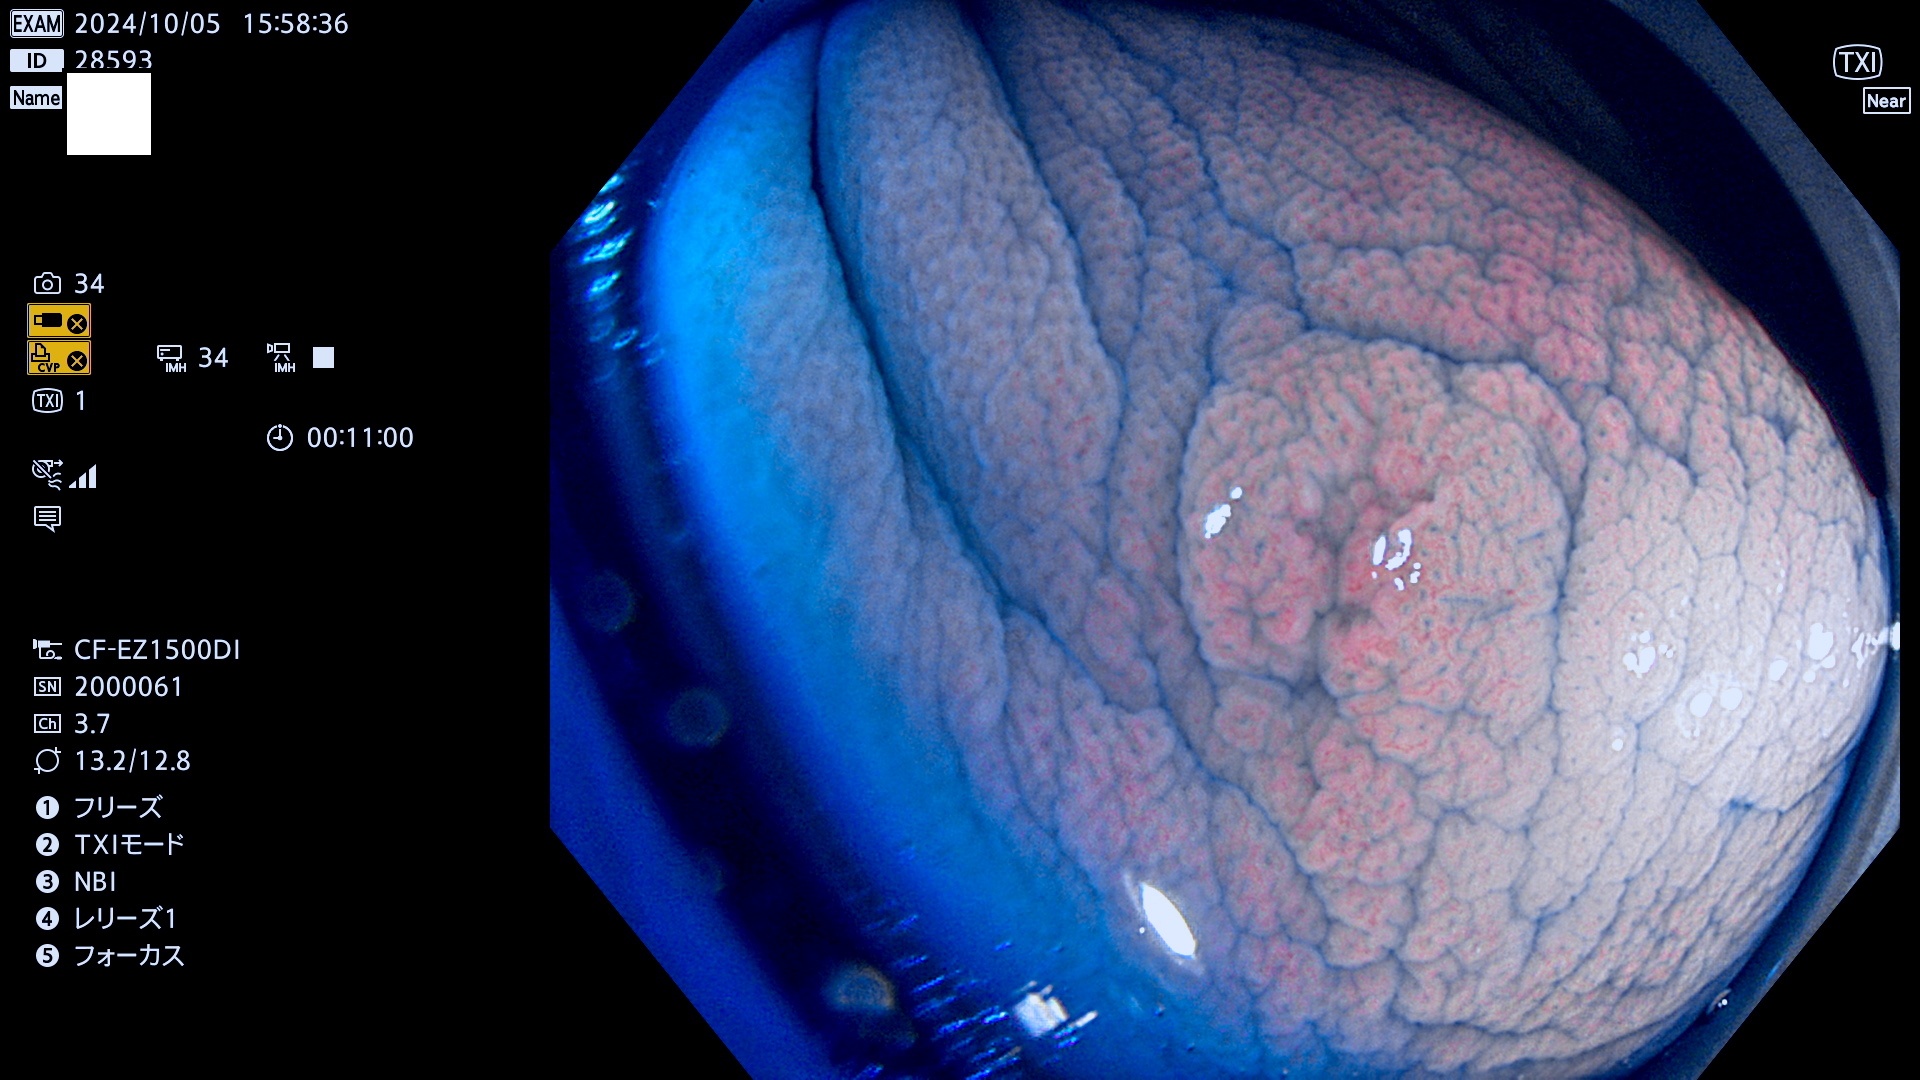

今週のUb、Uc型腺腫

完全に平坦な物をUb、陥凹している物をUcと呼びます。最も発見が難しく危険な病変です。

毎週の検査(木・金・土・日)に発見されたUb、Uc型・腺腫を、その週の日曜の夜にUPし1週間、提示します。

抽出の対象期間 2024年10月3日〜10月6日の4日間(48件の検査)9件 (9/48=18%)